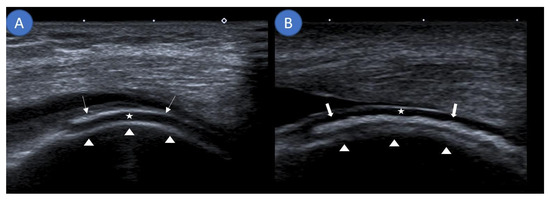

Musculoskeletal ultrasound examinations were performed by a board-certified musculoskeletal ultrasonographer with German Society for Ultrasound in Medicine (DEGUM) level III (highest level instructor) certification at the Clinic for Internal Medicine, Hematology, Nephrology, Infectiology and Rheumatology, Klinikum Ludwigshafen, Ludwigshafen, Germany, using an Aplio 400 Toshiba (Canon Medical Systems GmbH, Neuss, Germany) machine with linear or hockey stick transducers (5–14 MHz). Ultrasound examinations assessed for the DC sign and DoV as well as noted the presence of an iHE sign. The DC sign was defined as hyperechoic bands adjacent to hyaline cartilage (Figure 1A) [15]. If these hyperechoic signals could be confidently placed inside the cartilage and not on a tangent with it, they were termed as the iHE sign (Figure 1B), an ultrasound finding previously described as specific for CPPD [16]. Figure 1 further clarifies the differentiation between the DC sign and the iHE sign. DoV was graded on a 0–3 scale with 0 having no Doppler signal, grade 1 demonstrating three or less isolated Doppler signals, grade 2 demonstrating three or more distinct Doppler signals, and grade 3 demonstrating multiple converging Doppler signals [17]. Ultrasound was performed prior to arthrocentesis; thus, the examiner was blinded to the final diagnosis.

Figure 1. Differentiating the double contour sign from an intracartilaginous hyperechogenicity. (A) Sagittal ultrasound demonstrating monosodium urate deposits (arrows) as a hyperechoic band running parallel to the echo-free hyaline cartilage (star) at the suprapatellar knee joint. Together with the hyperechoic margin created by the femur (arrow heads), this forms the double contour sign. (B) Sagittal ultrasound along the lateral femoral condyle showing an intracartilaginous hyperechogenicity (thick arrows) visualizing calcium pyrophosphate deposits consistent with the intracartilaginous hyperechogenicity sign.